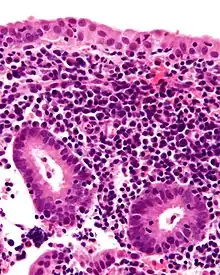

| Micrograph showing a chronic endometritis with the characteristic plasma cells. Scattered neutrophils are also present. H&E stain. | |

Chronic endometritis

Chronic endometritis is characterized by the presence of plasma cells in the stroma. Lymphocytes, eosinophils, and even lymphoid follicles may be seen, but in the absence of plasma cells, are not enough to warrant a histologic diagnosis. It may be seen in up to 10% of all endometrial biopsies performed for irregular bleeding. The most common organisms are Chlamydia trachomatis (chlamydia), Neisseria gonorrhoeae (gonorrhea), Streptococcus agalactiae (Group B Streptococcus), Mycoplasma hominis, tuberculosis, and various viruses. Most of these agents are capable of causing chronic pelvic inflammatory disease (PID). Patients with chronic endometritis may have an underlying cancer of the cervix or endometrium (although infectious cause is more common). Antibiotic therapy is curative in most cases (depending on underlying cause), with fairly rapid alleviation of symptoms after only 2 to 3 days. Women with chronic endometritis are also at a higher risk of pregnancy loss and treatment for this improves future pregnancy outcomes.[17][18]